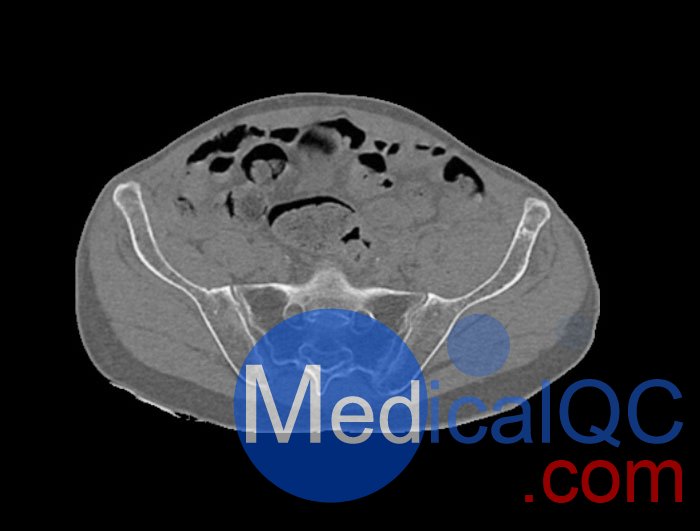

左側(cè)股骨頸移位骨折。

診斷特征

骨骼和軟組織的逼真模擬。

WEK54-01股骨頸骨折骨盆模型,WEK54-01骨盆模體成像效果圖: